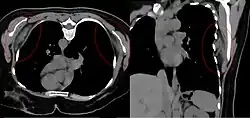

| Bilateral elastofibroma dorsi in native computed tomography: left image axial in prone position (for biopsy), right image oblique coronal view. |

By computed tomography, there is a poorly circumscribed, heterogeneous soft tissue mass, with a signal intensity similar to skeletal muscle. The fact that the lesion may be bilateral, helps eliminate a sarcoma from further consideration.[6] At US, elastofibromas are depicted deep to the musculature as a multilayered pattern of hypoechoic linear areas of fat deposition intermixed with echogenic fibroelastic tissue.[7] The mass often protrudes from the subscapular region upon shoulder abduction, allowing better delineation of the finding.[8]